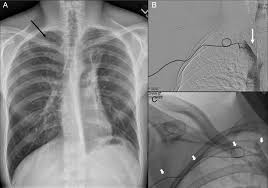

The picc line travels from the point of insertion to the mid chest, so the length depends on the size of the person and the site of entry. Aug 29, 2019 · your doctor might recommend a picc line if your treatment plan requires frequent needle sticks for medicine or blood draws. It is slowly advanced into the blood vessel, where it goes up the arm and then makes its way toward the heart. See full list on verywellhealth.com Nov 05, 2015 · i am wondering what the general consensus is about how long picc lines should stay in? See full list on verywellhealth.com Liquid nutrition may be given daily through a vein in those with difficulty eating or absorbing nutrients. In addition, people might need a picc line in the following situations:

An infection may form at the insertion site, an event that is more likely the longer the picc line remains in place. The picc line may be trimmed to a shorter length if necessary, especially if you are petite. Removal of a picc line is quick and typically painless. You will need to cover their picc site with plastic wrap or a waterproof bandage for showering. It should look the same as it did when it was inserted, with no missing pieces that could potentially be left inside the body. A picc line can have multiple ports, al. Most patients say that it feels strange to have it removed, but it is not uncomfortable or painful. If there is a complication with a picc line, it may need to be removed or adjusted, or additional treatments may be required. Poor venous access requiring multiple iv site changes and therapies lasting less than 30 days • may use for lab draws A picc can also spare your veins and blood vessels from the irritating effects of iv medications. A picc can be used in the hospital setting, nursing facility, or at home and can stay in place for weeks or months, if needed. Using sterile technique, the picc line is gently inserted into the vessel. If the line is too close to the heart, or in the heart, it can irritate the heart and cause a cardiac arrhythmia, an abnormal.

Blood clots can form on the tip of the picc line. Aug 29, 2019 · your doctor might recommend a picc line if your treatment plan requires frequent needle sticks for medicine or blood draws. How long can a picc line stay in? If these clots break free, they can travel through the heart to the lung, a condition called a pulmonary embolism (pe). they can also form in the arm around the line and may cause vein inflammation. Nov 05, 2015 · i am wondering what the general consensus is about how long picc lines should stay in? You will need to cover their picc site with plastic wrap or a waterproof bandage for showering. Oct 07, 2020 · a picc must be ordered by your primary physician or surgeon or their consulting colleague. Not sure how you are talking about an exchange but usually this is an exchange over a wire or through an introducer. Serious bacterial or fungal infectionsmay require daily iv medications for several weeks or more. Most patients say that it feels strange to have it removed, but it is not uncomfortable or painful. The picc line may be trimmed to a shorter length if necessary, especially if you are petite. The benefit of a picc is that the catheter can remain for a long period, typically two to six weeks, over which a course of medication such as antibiotics can be delivered. Ive read online that they shouldnt't be left in for longer than one year.

The benefit of a picc is that the catheter can remain for a long period, typically two to six weeks, over which a course of medication such as antibiotics can be delivered. If the line is too close to the heart, or in the heart, it can irritate the heart and cause a cardiac arrhythmia, an abnormal. The picc line may be trimmed to a shorter length if necessary, especially if you are petite. Once the picc is in the appropriate place, it can be secured to the skin outside of the insertion site. most picc lines are sutured in p. While picc lines can sometimes have complications, the potential benefits usually exceed the risks and they're a reliable way to deliver medications and monitor health conditions.1 once a picc line is in place, you will not have to deal with the irritation or sensitivity of repeated needle pokes in order to receive treatments or have blood drawn for testing. Once the picc is out, the end of the line is inspected. Feb 05, 2015 · for any catheter that is open, patent (meaning flushes easily with a good blood return and not signs/symptoms of any problem), it should remain in place until the need has finished. What does picc line stand for?